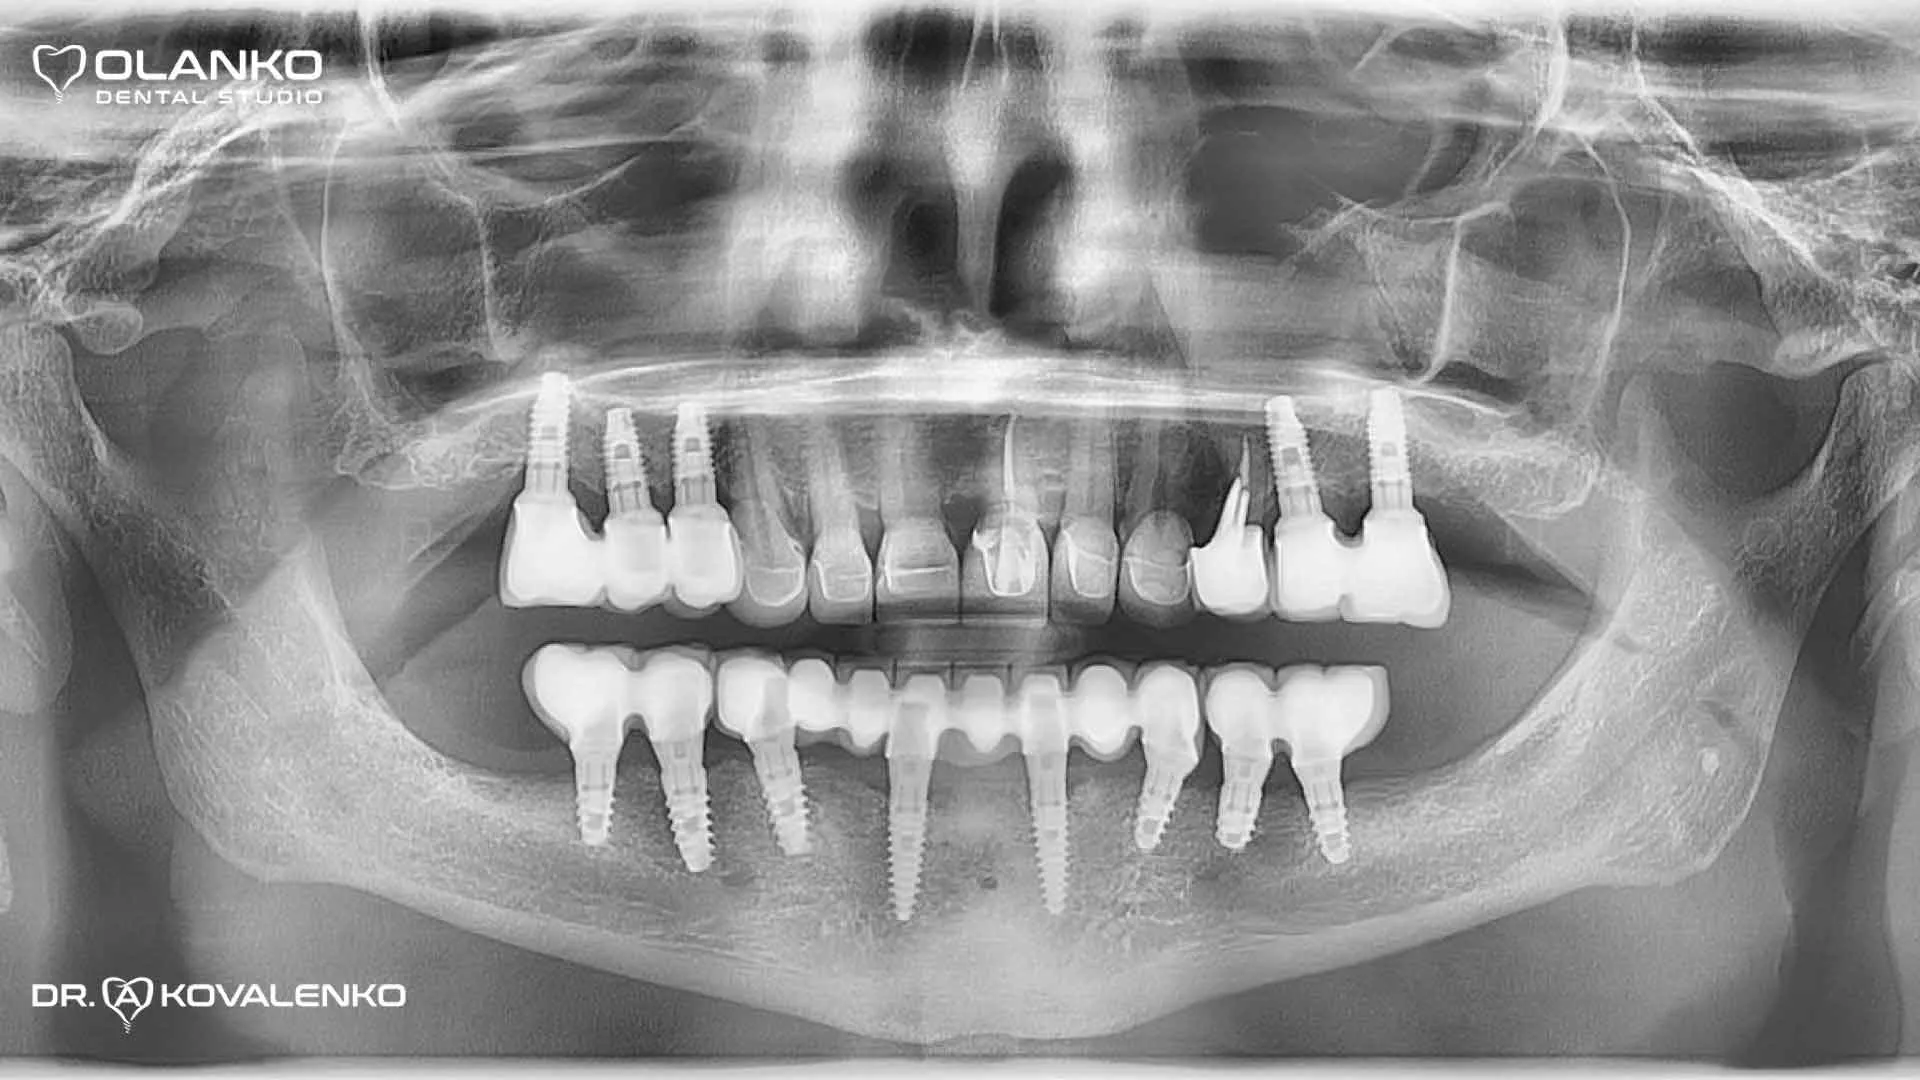

Приклад протезування беззубої щелепи з використанням зубних імплантатів, виконано в клініці Olanko dental studio (Оланко) в 2012-му році.

Пацієнту було встановлено 8 імплантатів на нижню щелепу та 5 імплантатів на верхню щелепу, а також встановлені протези та коронки з опорою на імплантати, які є аналогом штучних коренів зубів.

Контрольний панорамний рентген знімок через 8 років після протезування, стабільний рівень кістки навколо зубних імплантатів